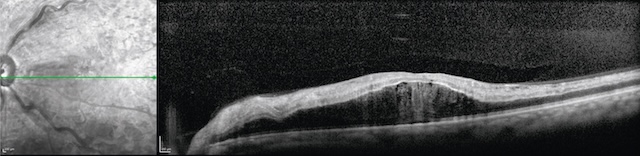

Image en coupe obtenue par tomographie en cohérence optique (OCT) de l’œil gauche, montrant un œdème maculaire central. Sur la partie gauche de l’image, un cliché en infrarouge structurel localise la coupe transversale, tandis que la partie droite révèle clairement un épaississement rétinien au niveau de la macula. La fovéa normale, habituellement creusée, est ici totalement comblée par une accumulation de fluide intrarétinien, formant un bombement central. De multiples cavités hypo-réflectives sont visibles dans les couches internes, caractéristiques d’un œdème cystoïde. La stratification rétinienne reste partiellement identifiable mais apparaît déformée, traduisant une atteinte fonctionnelle probable de la vision centrale. L’ensemble suggère une rétinopathie œdémateuse active nécessitant un traitement ciblé.